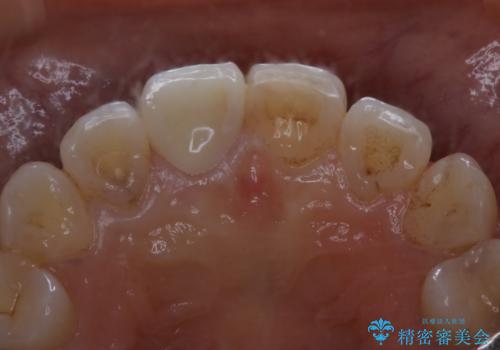

- プラスチックで治療している前歯が何度も欠けてしまうとお悩みで来院された方です。

歯全体を覆うクラウンにて治療を行いました。

- 14万円(オールセラミッククラウンスペシャル13万円・仮歯1万円)費用は治療当時の料金となります

前歯1本のみの被せ物治療を行う場合、他の歯を参考に歯の色や形を忠実に再現することが重要です。オールセラミッククラウン(スペシャル・エクセレント)は、事前に歯科技工士との打ち合わせを行うことで、歯の色や形、さらには患者様のご希望も聴取したうえでクラウンを作製することが可能です。